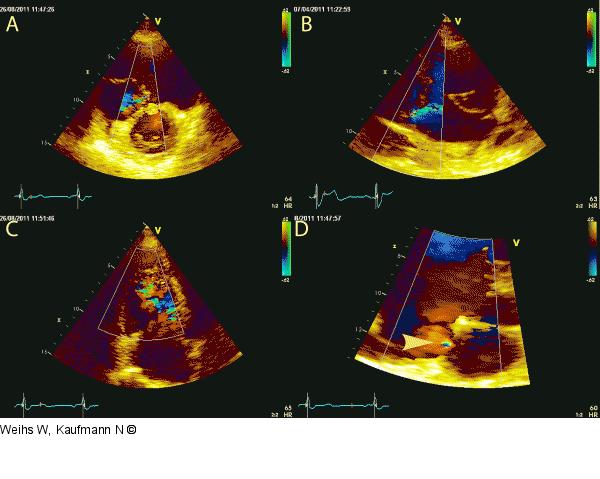

Abbildung 7: Farbdoppler Im Farbdoppler milde Trikuspidalinsuffizienz im parasternalen Querschnitt (A), im rechtsventrikulären Einflusstraktschnitt (B) und im apikalen Schnitt (C). Turbulenter Farbdopplerfluss im Bereich des interatrialen Septums bei bekanntem kleinen ASD II (D). |